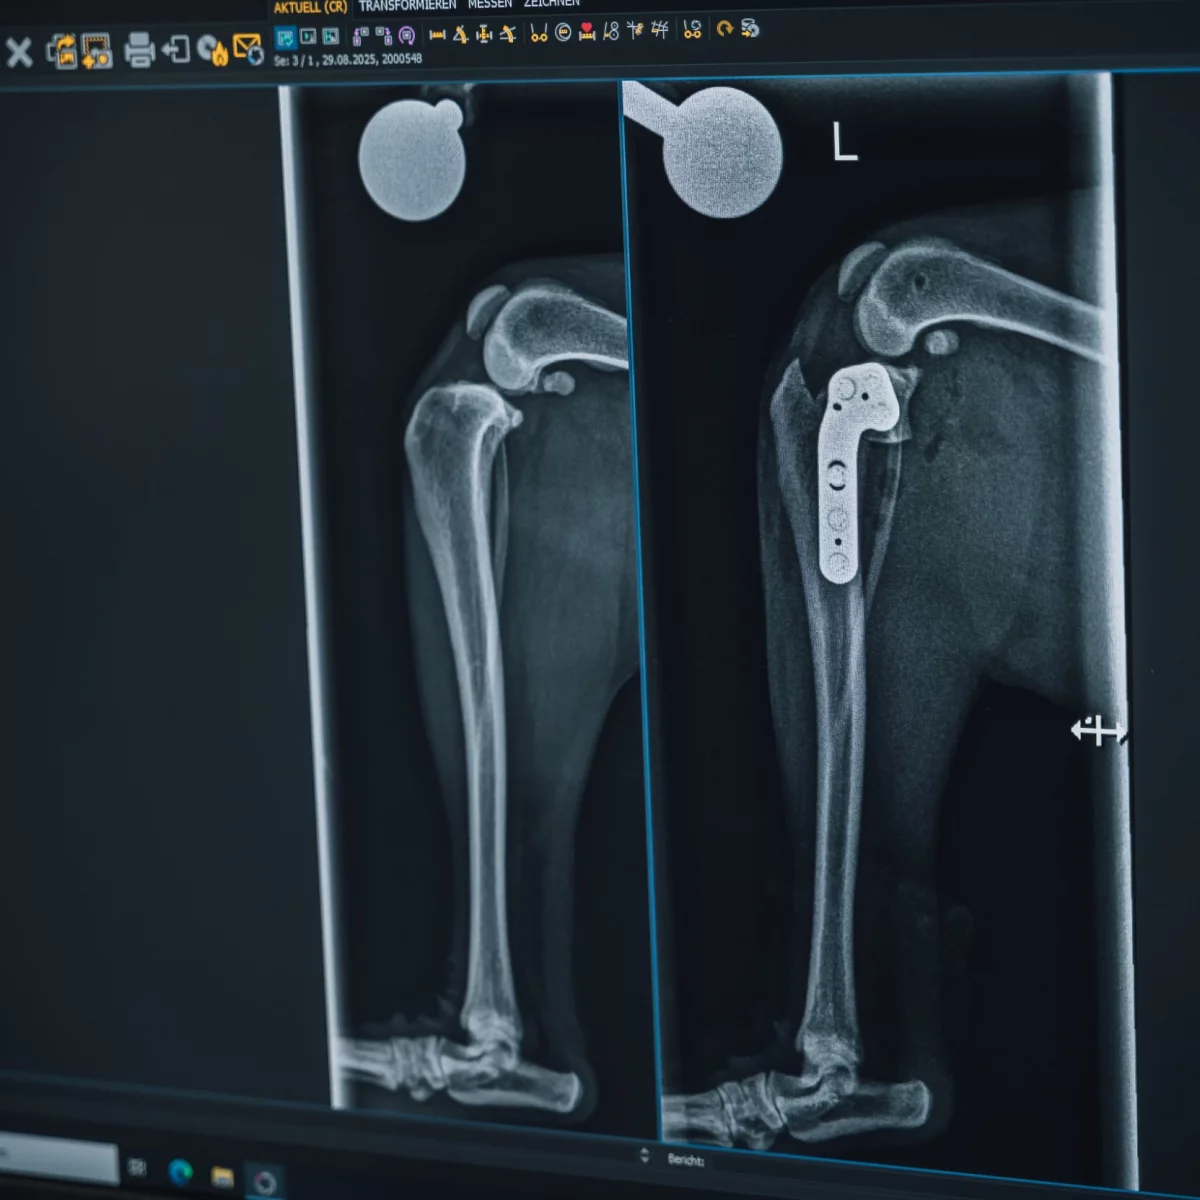

Beweglichkeit wiederherstellen – mit präziser Chirurgie an Knochen, Gelenken, Bändern, Muskeln und Sehnen

Unsere orthopädischen Operationen sorgen für neue Beweglichkeit und helfen deinem Tier bei Erkrankungen oder Verletzungen zurück in ein aktives Leben.

Wann ist eine orthopädische Operation notwendig?

Wenn Gelenke, Knochen, Bänder, Muskeln oder Sehnen durch Verletzungen, Verschleiß oder Fehlstellungen starke Schmerzen oder Bewegungseinschränkungen verursachen, kann eine Operation erforderlich sein.